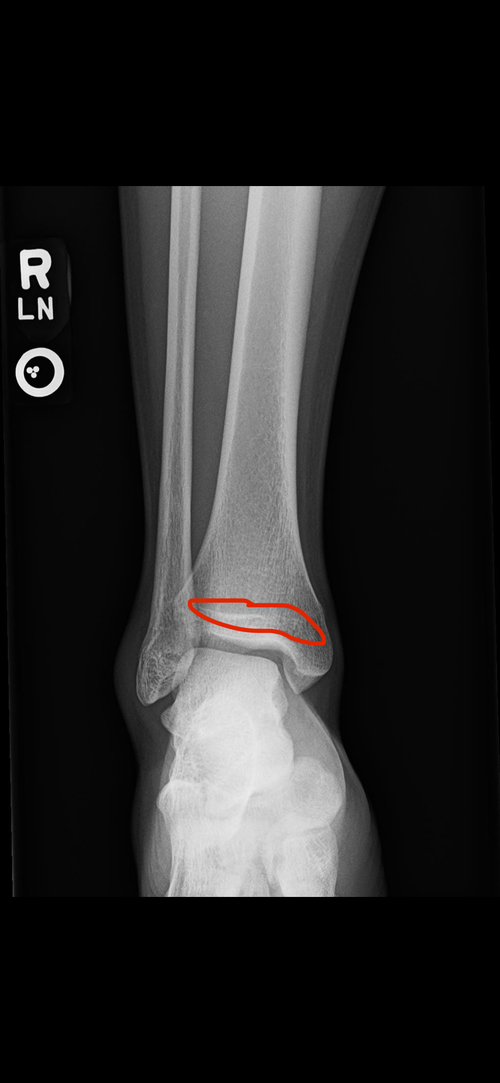

So I started my hgh cycle last week and slowly increasing the dose. Since my plates are still open I ordered arimidex with it I’ll be starting with .25 mg eod before blood work but yall lmk if it’s worth it with these x rays. They’re somewhat open but ik other plates could be more open. (Hgh attached to so yall know Im deadass)